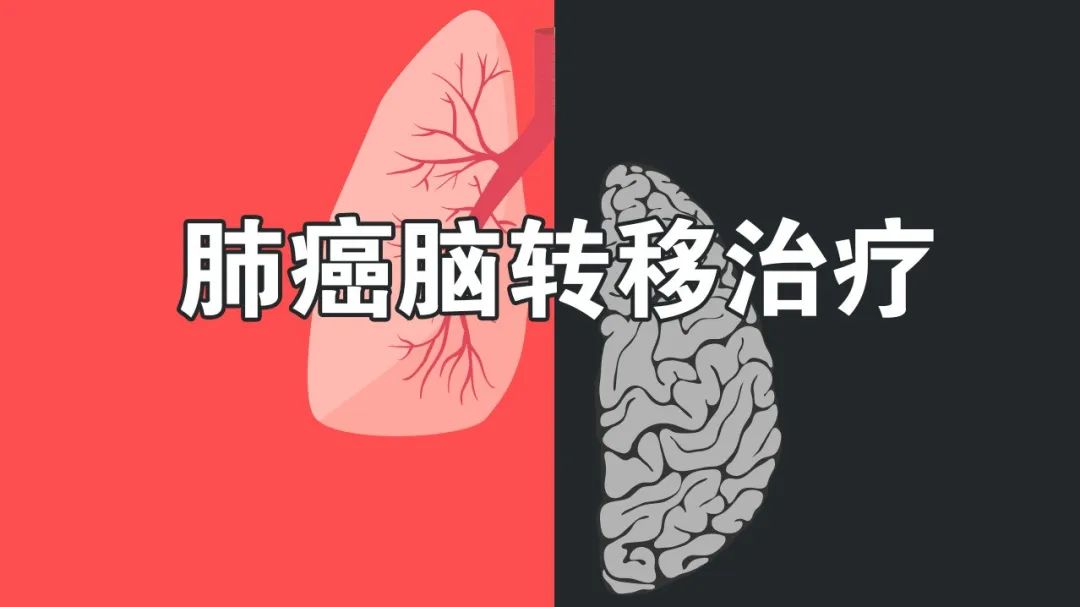

谁对肺癌脑转移效果更胜一筹?全脑放疗还是立体定向放射治疗?...

谁对肺癌脑转移效果更胜一筹?全脑放疗还是立体定向放射治疗?...

最新肺癌脑转移中国治疗指南

最新肺癌脑转移中国治疗指南

肺癌脑转移中国治疗指南(2021年版)

肺癌脑转移中国治疗指南(2021年版)

肺癌脑转移治疗指南,一图读懂!

肺癌脑转移治疗指南,一图读懂!

最全“肺癌脑转移”全面解读,延长生存期的要点...

最全“肺癌脑转移”全面解读,延长生存期的要点...